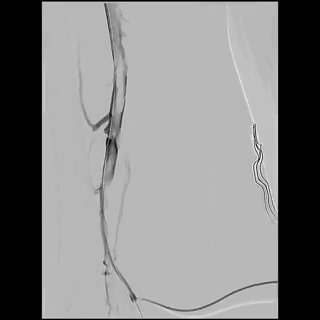

Right internal jugular vein (IJV) and popliteal vein large bore access was obtained with a 14Fr sheath and a 16Fr ClotTriever sheath respectively. Initial venogram showed extensive thrombosis from the below knee popliteal vein to the IVC filter with flow stasis of the intravenous contrast.

Through and through wire was achieved from popliteal to IJV and the 14fr IJV sheath was advanced past the IVCF struts to act as a protection for the basket and coring element of the ClotTriever for thrombectomy of the IVC and iliofemoral veins as several passes were made. There was satisfactory clearance of clots from the left iliofemoral veins. Aspiration of the IVCF was then performed with a FlowTriever 16 catheter but there was incomplete thrombectomy with some of the remnant clots being pushed above the IVC filter. The IJV sheath was upsized to 16F over and the sheath was used to protect the ClotTriever as it passed though the filter. The through and through Rosen wire (Cook Medical, Bloomington, Indiana) was subsequently pulled back from the IJV and cannulated into the right subclavian vein. The ClotTriever was then deployed next to the 16Fr sheath above the filter as an embolic protection device. The thrombosed IVC filter was then retrieved with a Clover snare (Cook Medical, Bloomington, Indiana). From the IJV sheath, FlowTriever disks were deployed and further thrombectomy of the remnant IVC thrombus was performed which yielded even more thrombus.

Completion venogram showed brisk return of flow and patency.